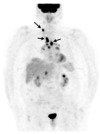

Sarcoidosis is a multi-system disease of unknown etiology characterized by the formation of granulomas in various organs. It affects people of all ethnic backgrounds and occurs at any time of life but is more frequent in African Americans and Scandinavians and in adults between 30 and 50 years of age. Sarcoidosis can affect any organ with a frequency varying according to ethnicity, sex and age. Intrathoracic involvement occurs in 90% of patients with symmetrical bilateral hilar adenopathy and/or diffuse lung micronodules, mainly along the lymphatic structures which are the most affected system. Among extrapulmonary manifestations, skin lesions, uveitis, liver or splenic involvement, peripheral and abdominal lymphadenopathy and peripheral arthritis are the most frequent with a prevalence of 25-50%. Finally, cardiac and neurological manifestations which can be the initial manifestation of sarcoidosis, as can be bilateral parotitis, nasosinusal or laryngeal signs, hypercalcemia and renal dysfunction, affect less than 10% of patients. The diagnosis is not standardized but is based on three major criteria: a compatible clinical and/or radiological presentation, the histological evidence of non-necrotizing granulomatous inflammation in one or more tissues and the exclusion of alternative causes of granulomatous disease. Certain clinical features are considered to be highly specific of the disease (e.g., Löfgren's syndrome, lupus pernio, Heerfordt's syndrome) and do not require histological confirmation. New diagnostic guidelines were recently published. Specific clinical criteria have been developed for the diagnosis of cardiac, neurological and ocular sarcoidosis. This article focuses on the clinical presentation and the common differentials that need to be considered when appropriate.